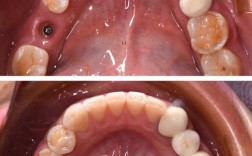

- 牙龈形态异常: 种植体位置不正可能导致牙龈乳头形态不佳、牙龈黑三角、牙龈红肿或萎缩,影响笑容美观。

- 牙冠形态和位置异常: 即使牙冠制作精良,如果下面的种植体位置歪斜,最终修复出来的牙冠在排列、角度上也会显得不自然、不协调。

- 清洁困难: 位置不正的种植体和修复体可能形成难以清洁的死角,容易堆积食物残渣和菌斑,增加种植体周围炎的风险,这是导致种植牙远期失败的主要原因之一。